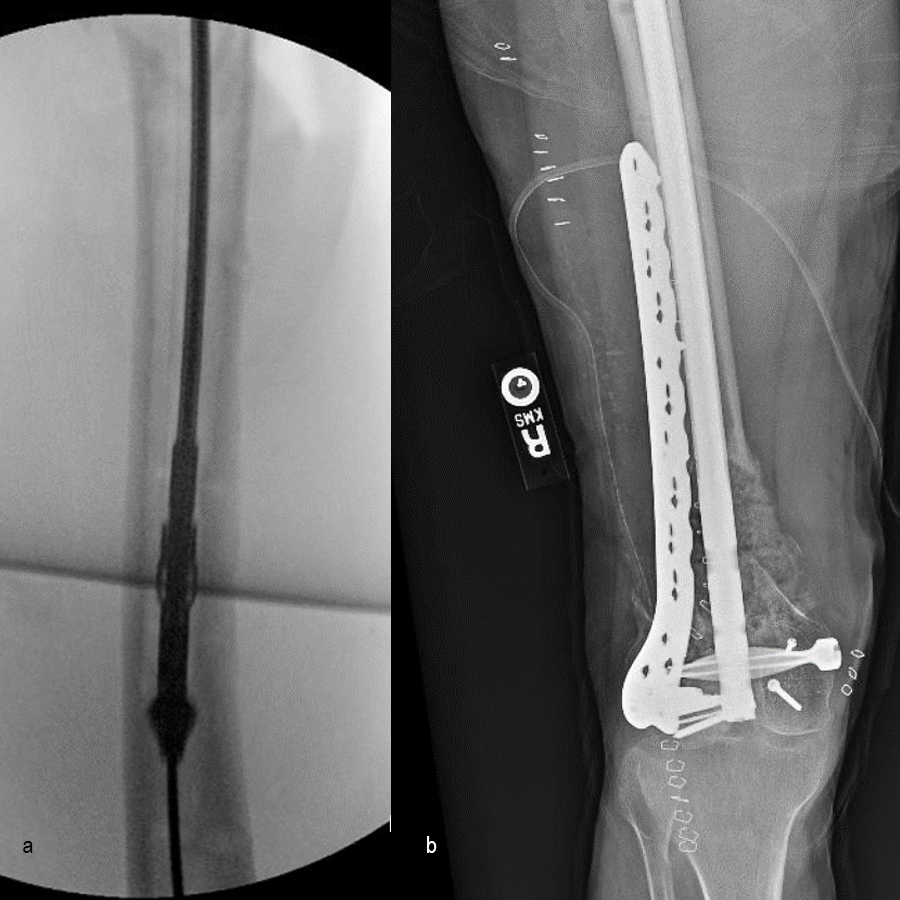

At 5 days post-initial surgery, the lung injury was improved, so the patient underwent open reduction and internal fixation (ORIF) of the right distal femur with resection of devitalized bone and cement spacer placement (Fig 7). Definitive fixation of the other fractures (ankle and ribs) was undertaken over time.

Following the advent of Covid-19 in early 2020, the patient was lost to follow-up for almost one year and was eventually seen again in December 2020 (Fig 8). At this follow-up, a CT scan was planned for the right distal femur and a graft cage ordered. Surgery was scheduled for early 2021.

At the 3-week follow-up (post-graft cage, Fig 12), the patient’s wounds were healthy. He had a range of motion (ROM) of 0–80 in his right knee. He was allowed weight bearing as tolerated (WBAT) with crutches.